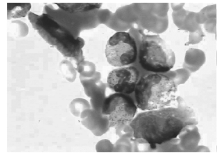

骨髓细胞学检查:增生明显活跃, 粒细胞系统占46.5%, 红细胞系统占19%, 粒∶ 红=2.45∶ 1。粒系比例大致正常, 晚幼粒比例增高, 可见双核, 胞浆空泡。红系比例大致正常, 可见巨幼样变、双核红。片中可见一类不明细胞占0.175, 多散在分布, 少数灶性分布, 该类细胞胞体大, 形状不规则, 胞浆丰富, 灰蓝色不透明, 可见少许粗大紫红色颗粒, 可有空泡, 胞核不规则, 染色质粗网状, 可见核仁1个或数个(见图1)。易见吞噬血细胞现象, 为一类组织细胞, 胞体大, 边缘不整, 胞浆丰富, 淡灰色, 内含吞噬的幼红及幼粒细胞, 或为细胞碎片及空泡, 胞核圆, 常偏于一侧, 染色质粗网状(见图2)。诊断:淋巴瘤骨髓侵犯伴噬血细胞增多。

有关SPTCL的骨髓侵犯, 国内外报道很少, Haque等[7]对6例患者进行了骨髓T细胞基因分析, 1例出现T细胞的单克隆表达。林聪猛等[5]报道8例患者均无骨髓侵犯, 但1例可见骨髓中组织细胞吞噬红细胞现象。本例骨髓中可见异常淋巴细胞, 同时易见噬血现象。